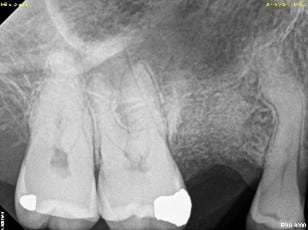

An internal sinus lift is drilled into the membrane when drilling the implant site called an osteotome (usually used to place one or two implants). The internal sinus lift (see yellow arrows) is a more conservative approach used mainly with simultaneous implant placement.

An example of an internal sinus lift can be seen below:

Stage 1: Hopelessly Fractured Tooth

Stage 2: Tooth Extracted, Bone Graft Placed

Stage 3: Implant Placed with a Sinus Lift at the Top